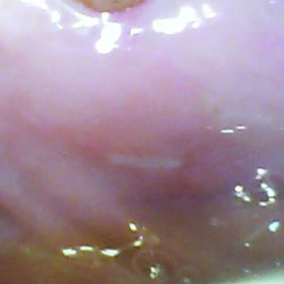

「アフタ」とは、口の中にできる直径

5~ 6ミリぐらいの白い潰瘍のことです。